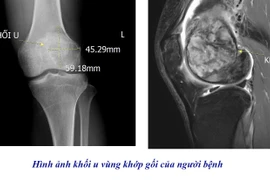

Sau ca phẫu thuật, chị Vương Thị Cẩm L. giảm đau lưng rõ rệt, cảm giác tê chân trái cải thiện đáng kể và không xuất hiện tổn thương thần kinh mới. Kết quả giải phẫu bệnh cho thấy: khối u là u bao dây thần kinh ngoại biên ác tính (MPNST – Malignant Peripheral Nerve Sheath Tumor), một dạng ung thư hiếm gặp, có tốc độ phát triển nhanh và tiên lượng nặng. Hiện chị L. đang được theo dõi và điều trị bổ sung bằng hóa – xạ trị theo phác đồ phù hợp.